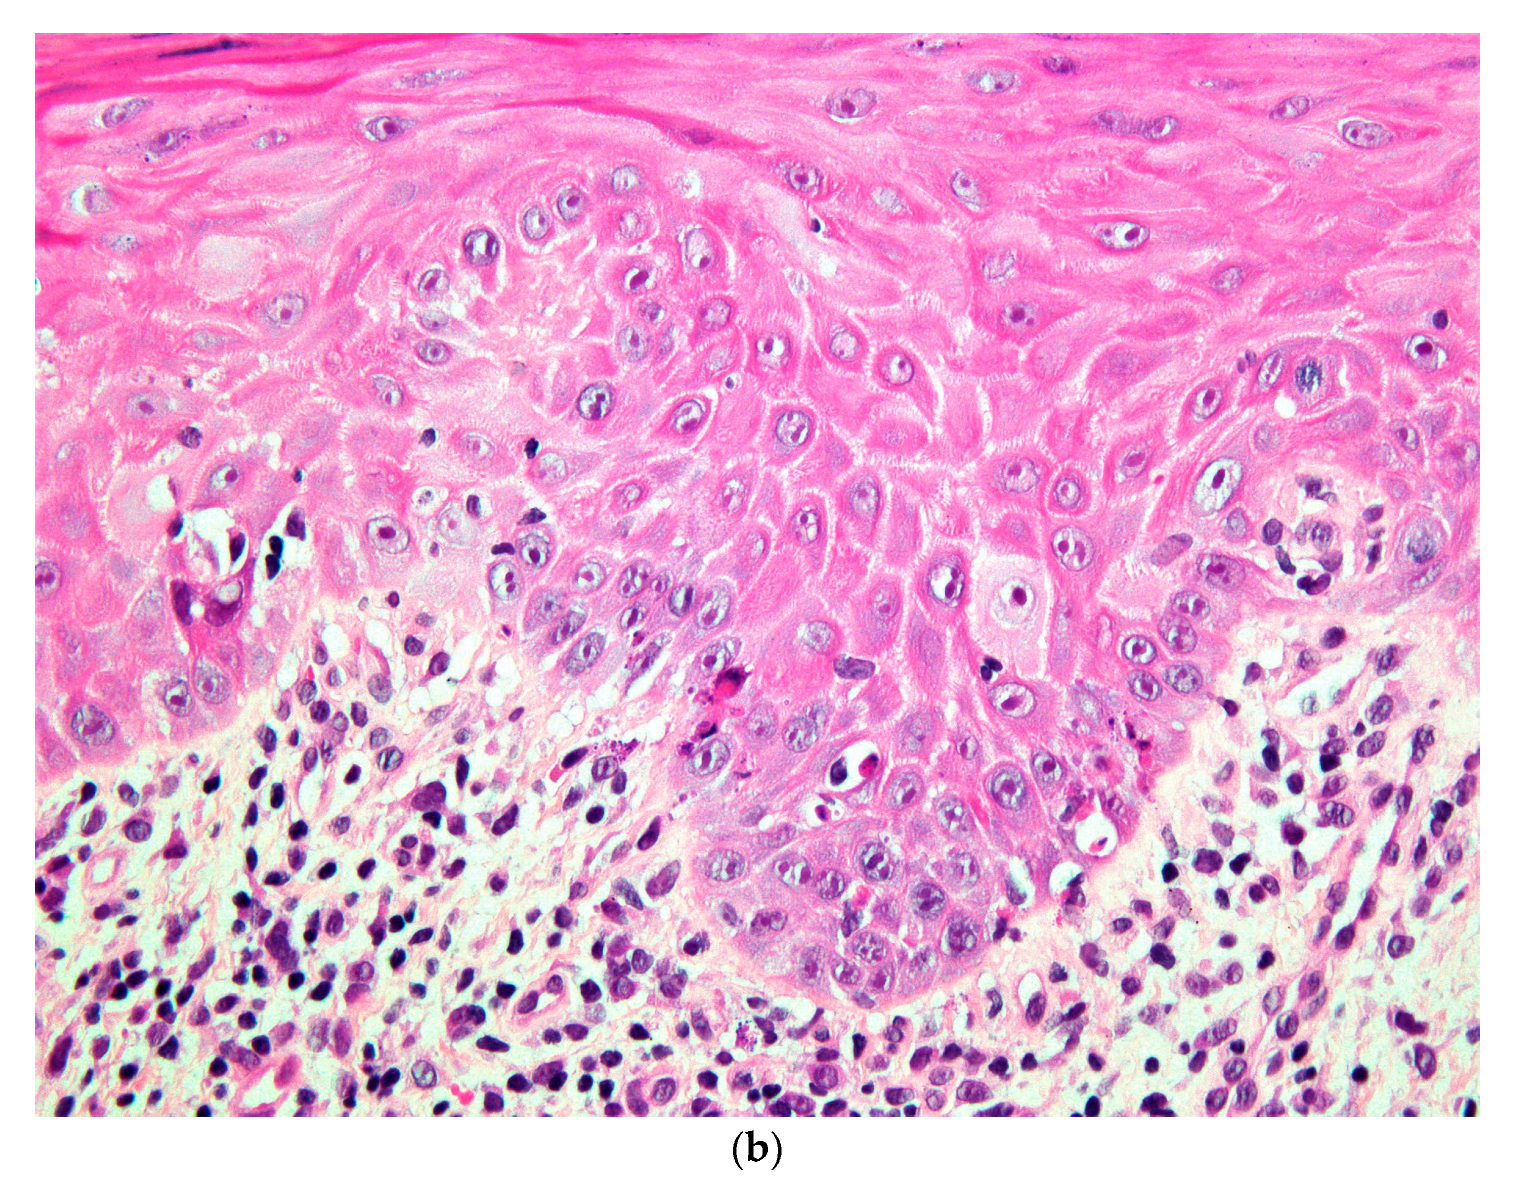

| Present case | M, Caucasian, 59 y | Buccal ulceration Keratotic striae on the lip, buccal mucosa and tongue | Gout | LP versus lichenoid reaction | Complete healing |